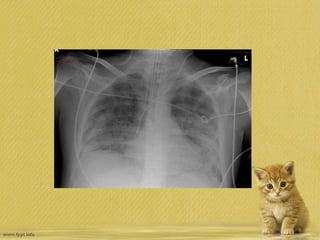

• Kardiyak gölge normal

• Bilateral diffuz infiltrasyonlar

• Plevral effüzyon yok